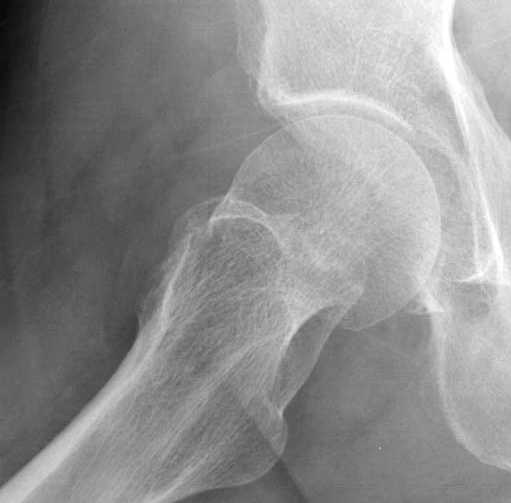

Почему неполный перелом? Я бы назвал его вколоченным!

Перелом конечно не вколоченный т.к. видно линию перелома и нет суперпозиции костной ткани.

Добрый день. Перелом коварный. Через время может произойти лизис в области "неполного" перелома и он превратиться в "полный" со всеми очевидными проблемами, тем более у пациента, склонного к питию. Если не разовьется делирий или после выхода из него, рекомендую внутренний остеосинтез винтами.

Профилактику дальнейшего раскола неполного перелома шейки провели тремя канюлированными шурупами.